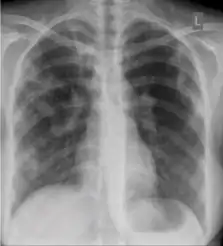

Dense homogenous opacity in right, middle and lower lobe of primary pulmonary TB.

Chest x-ray showing patchy opacification on the upper right and mid-zone lung with fibrotic shadows, as well as bilateral hilar lymphadenopathy.